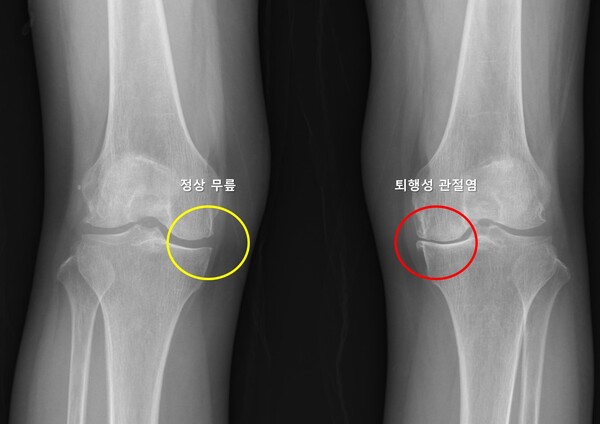

서울대병원, 반대쪽 무릎 퇴행성 관절염 발생 예측모델 개발

서울대병원 연구팀이 퇴행성 관절염 환자에서 반대쪽 무릎에 퇴행성 관절염이 발생할 가능성을 예측하는 머신러닝 기반 모델을 개발했다. 이번 연구는 두 개의 대규모 관절염 추적 연구 데이터를 기반으로 반대쪽 무릎에서의 병적 진행 가능성을 체계적으로 예측함으로써, 조기 개입을 통한 예방적 관리 전략의 길을 제시했다는 점에서 학술적 의의가 크다.

무릎 퇴행성 관절염은 연골의 점진적인 손상과 관절 구조물의 퇴행성 변화로 인해 발생하는 질환으로, 통증과 운동 제한을 유발하며 삶의 질을 크게 저하시킬 수 있다. 전 세계 인구의 약 16~30%에서 발생하며, 고령화 사회로 접어들면서 그 유병률은 꾸준히 증가하는 추세다. 많은 환자들이 한쪽 무릎에 관절염이 생긴 뒤 수년 내 반대쪽 무릎에서도 통증이나 구조적 변화가 나타나는 경험을 하지만, 이러한 양측성 진행이 모든 환자에게서 동일하게 나타나는 것은 아니며, 이를 예측하려는 연구는 부족한 상황이었다.